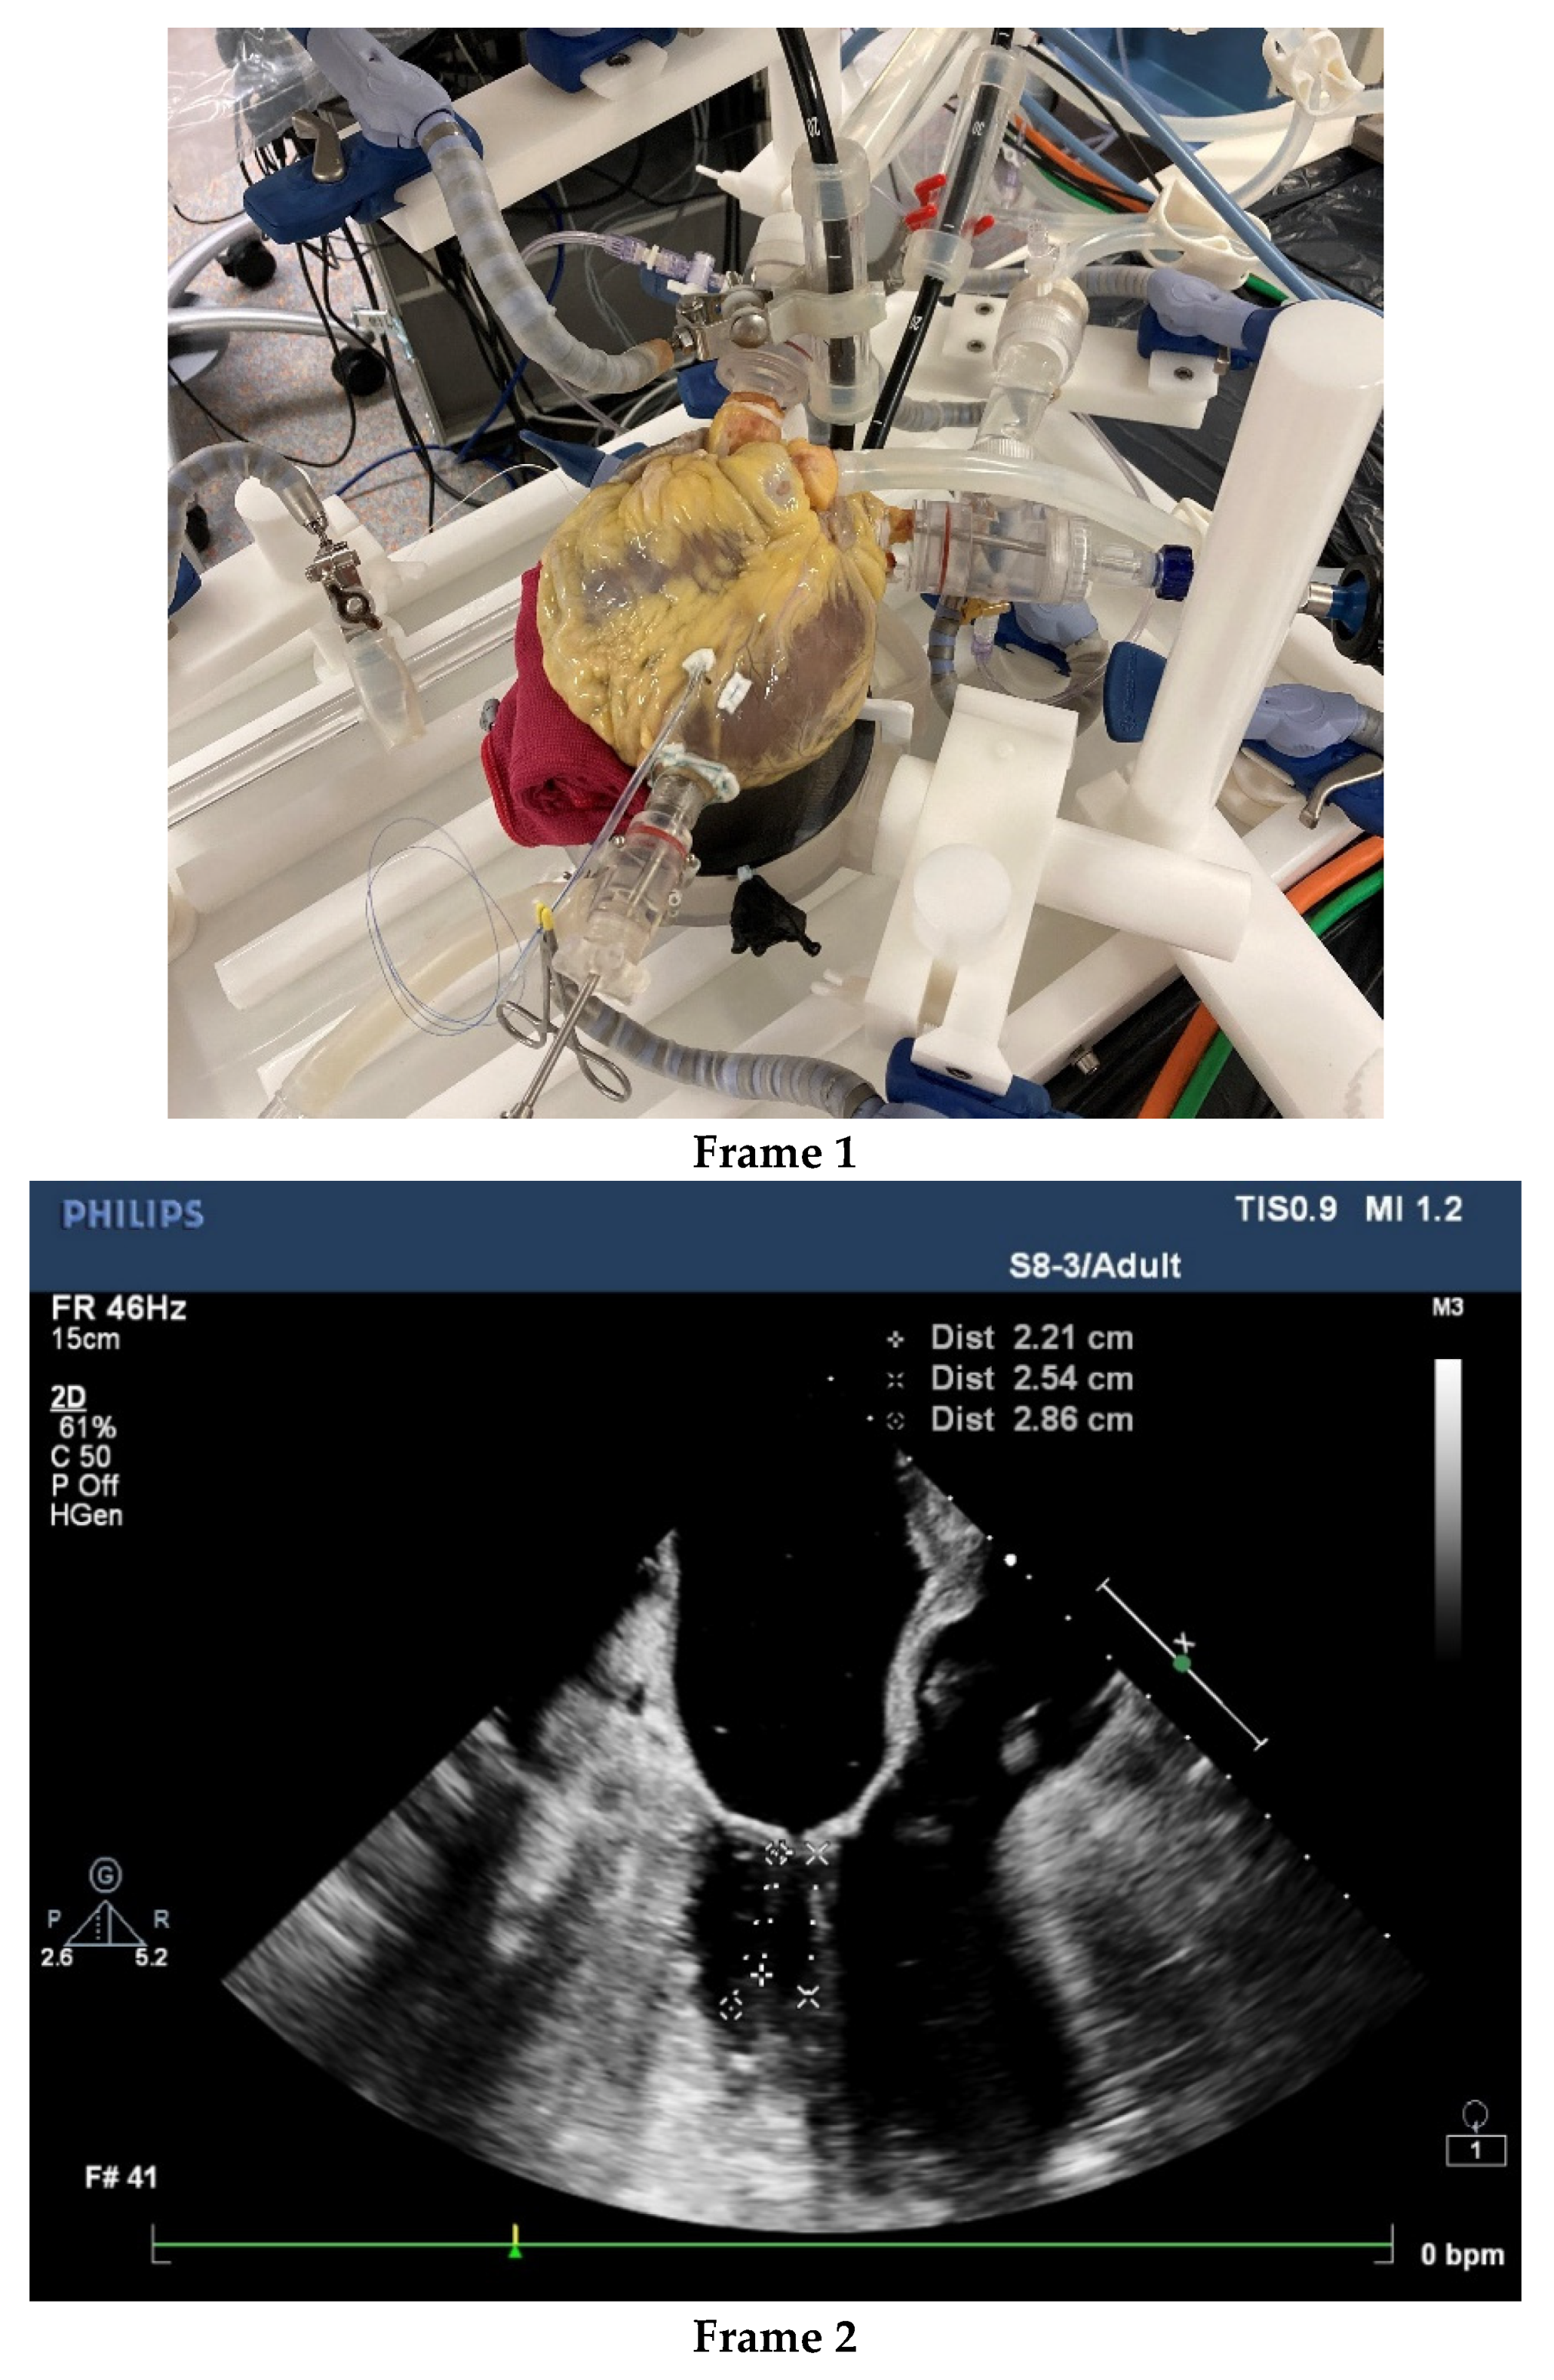

- Nia, P.S.; Daemen, J.H.; Maessen, J.G. Development of a high-fidelity minimally invasive mitral valve surgery simulator. J. Thorac. Cardiovasc. Surg. 2019, 157, 1567–1574. [Google Scholar] [CrossRef]

- Gollmann-Tepeköylü, C.; Holfeld, J.; Pölzl, G.; Metzler, B.; Hintringer, F.; Adukauskaite, A.; Stijnen, M.; van Tuijl, S.; Müller, L.; Grimm, M.; et al. Beating heart porcine high-fidelity simulator for the training of edge-to-edge mitral valve repair. Multimedia Man. Cardio-Thorac. Surg. 2018. [Google Scholar] [CrossRef]

- Leopaldi, A.M.; Wrobel, K.; Speziali, G.; van Tuijl, S.; Drasutiene, A.; Chitwood, W.R. The dynamic cardiac biosimulator: A method for training physicians in beating-heart mitral valve repair procedures. J. Thorac. Cardiovasc. Surg. 2018, 155, 147–155. [Google Scholar] [CrossRef]